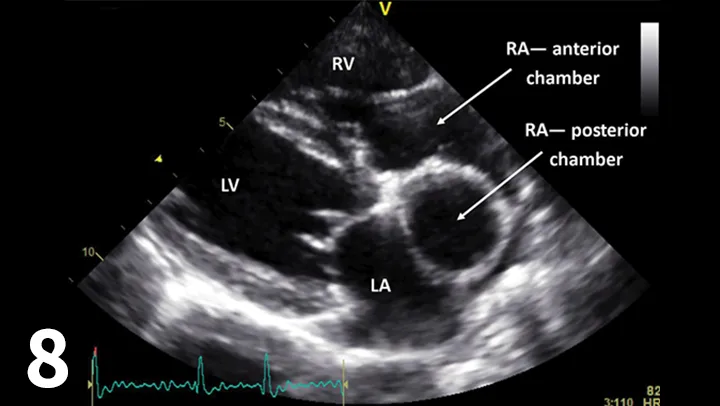

FIGURE 8

Right-sided long-axis view showing the 2 chambers of the right atrium (RA) with the left and right ventricles. (Ao = aorta; LA = left atrium)